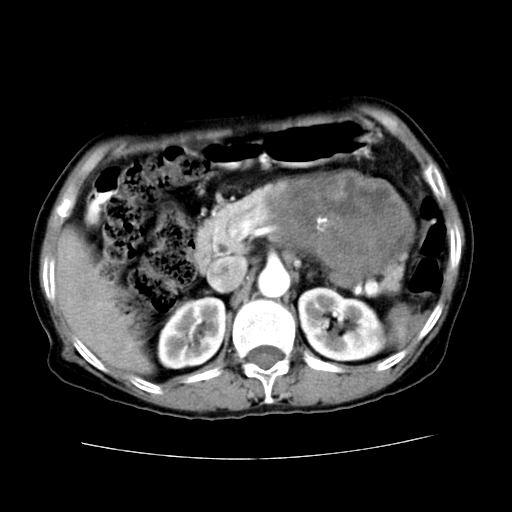

女性,72岁。

主诉中上腹部疼痛不适1年余。

胰腺尾部不规则巨大略低密度肿块,界限清楚,内密度不均,增强动脉期不均匀强化,门脉期明显退减并低于胰腺密度,肿瘤包埋于脾血管。多考虑;来源于胰腺尾部的“胰腺癌”。

1、这个病例确实有点难。影像主要显示胰腺体尾部占位,我们当初也是诊断胰体尾部囊腺癌可能性大,而且读片会上也很多人这么诊断的。

2、手术所见:打开腹腔发现胃与胰腺体尾部可见肿块,大小约10×8×11cm,质硬,不可推动,周围血供丰富。术中诊断:胃肿瘤侵及胰腺体尾部。

1)、胃小弯侧胃肠间质瘤(考虑恶性),瘤体大小13.5×7×6.5cm,上下切缘阴性。

2)、胃小弯1只、幽门下2只淋巴结慢性炎。免疫组化:cd117(+)、cd34(+)、sma(+)、desmin(-)、s-100(-)、ki-67<10%(+).

4、这个肿瘤太大了,而且密度不均性强化,从这点我们应该不能单纯诊断胰腺癌,而应想到目前流行的胃肠道间质瘤。这个肿瘤主要发生于胃壁浆膜层,所以显示与胃壁关系不是很紧密,故而大多认为是胰腺癌。